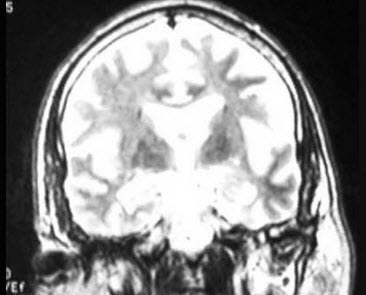

某老年男性以近事记忆障碍为早期和突出表现,余无明显不适,头颅MRI表现如图,考虑诊断为()

A.血管性痴呆

B.路易体痴呆

C.Pick病

D.Alzheimer病

E.CJD